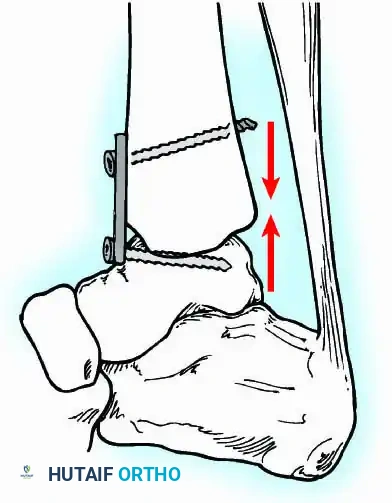

External Fixation

Historically pioneered by Charnley, external compression arthrodesis utilizes pins placed through the distal tibia and the body of the talus. Because Charnley's original uniplanar device lacked rotatory stability, Calandruccio designed a triangular frame to control motion in all three planes while applying massive compression.

Modern iterations, such as the Calandruccio II compression device, offer greater latitude in pin placement to avoid compromised skin. Ring or circular external fixators (Ilizarov, Taylor Spatial Frame) are the gold standard for salvage situations, including active infection, massive bone loss, or failed TAA, as they allow for simultaneous compression, deformity correction, and early weight-bearing.

Internal fixation is currently the preferred method for uncomplicated ankle arthrodesis due to higher union rates, superior patient comfort, and the elimination of pin-tract infections. Biomechanical studies demonstrate that crossed, large-diameter (6.5 mm or 7.3 mm) cannulated cancellous screws provide exceptional resistance to shear and torsional forces.

A standard construct involves two or three screws:

1. A "home run" screw directed from the posterior malleolus into the anterior neck of the talus.

2. A screw from the medial malleolus into the lateral body of the talus.

3. A screw from the anterolateral tibia into the medial talar body.